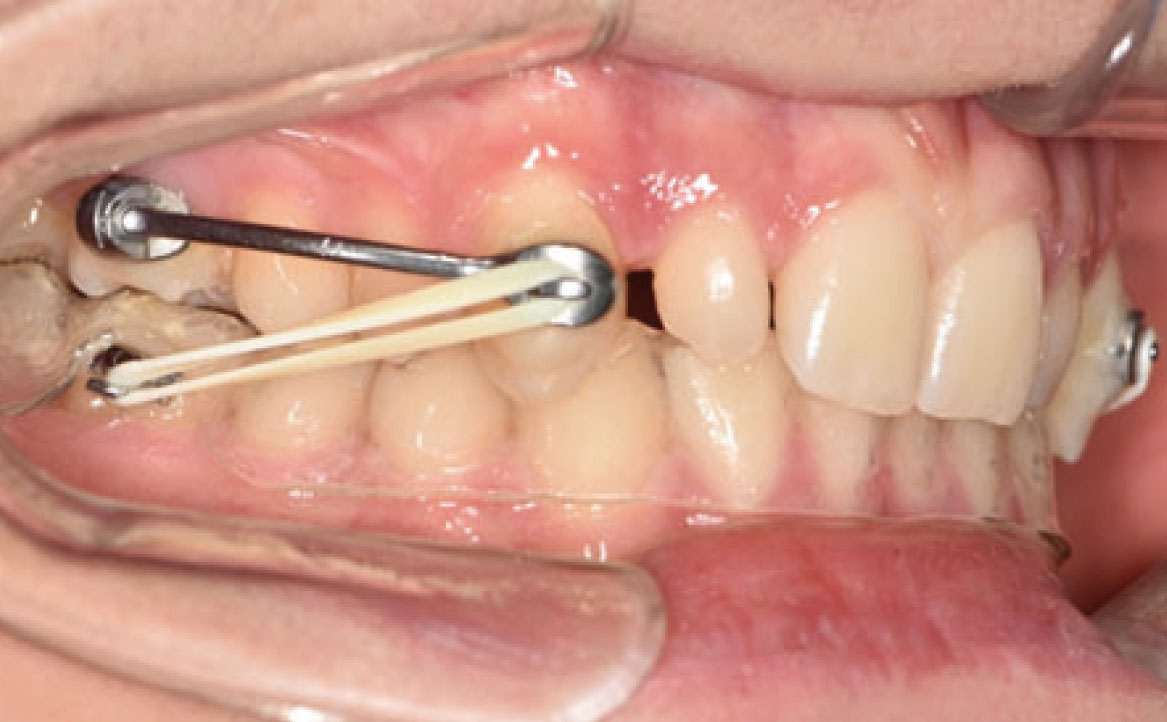

Un mese dopo, durante il secondo controllo, è stata raggiunta la posizione dei molari richiesta e, di conseguenza, il Carriere Motion è stato sospeso e si è iniziato il trattamento di ortodonzia fissa (fig. 4a-c).

Nello specifico, sono stati eseguiti bandaggi superiori e inferiori con tecnica Damon per l’allineamento e il livellamento delle arcate dentarie con l’aggiunta di rialzi occlusali, al fine di aprire il morso, ed elastici di classe II a tempo pieno (fig. 5a-c).